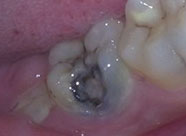

深齲蛀牙

牙髓發炎

根尖周炎

牙髓壞死

殘冠殘根